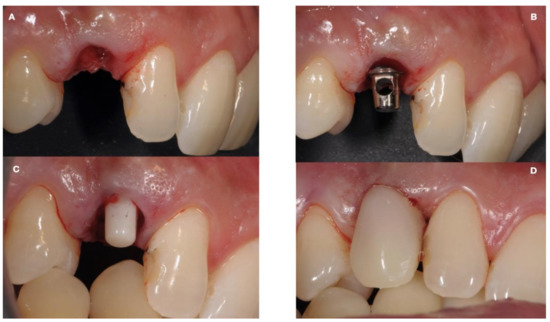

| (a) Surgical removal of the deciduous tooth and orthodontic extrusion, and taking in occlusion of the permanent canine |

| (b) Conservative treatment of the deciduous tooth living in situ with the impacted canine |

| (c) Removal of the deciduous tooth and involvement of the adjacent natural elements for a fixed conventional or adhesive bridge living in situ with the impacted canine |

| (d) Removal of the deciduous tooth and replacement with implant-borne-prosthesis living in situ with the impacted canine, accepting the compromise of involving the impacted tooth in the implant seating procedure |

| (e) Surgical removal of the impacted canine and, in a second stage, removal of the deciduous tooth and replacement with implant-borne-prosthesis |